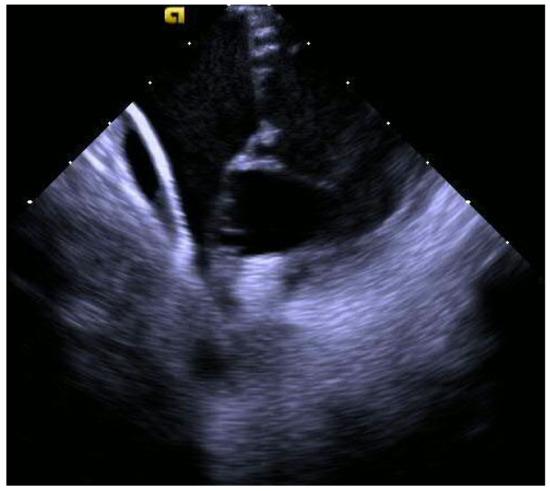

2.3. Echocardiography